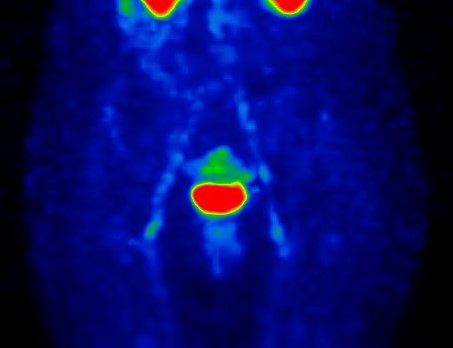

/ Obr.4.: SPECT krevního poolu v MIP projekci při kontrolní scintigrafii – normální nález.

/

Pro nově vzniklé bolesti rukou a loketních kloubů byla odeslána po 8 měsících na scintigrafii skeletu k potvrzení/vyloučení synovialitis postižených kloubů. Zároveň byla nahrána i oblast pánve, kde jsme neprokázali zvýšený krevní pool v oblasti obou SI skloubení.